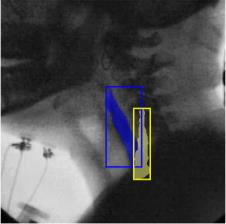

The videofluoroscopic swallowing study (VFSS) is a gold-standard imaging technique for assessing swallowing, but analysis and rating of VFSS recordings is time consuming and requires specialized training and expertise. Researchers have recently demonstrated that it is possible to automatically detect the pharyngeal phase of swallowing and to localize the bolus in VFSS recordings via computer vision, fostering the development of novel techniques for automatic VFSS analysis. However, training of algorithms to perform these tasks requires large amounts of annotated data that are seldom available. We demonstrate that the challenges of pharyngeal phase detection and bolus localization can be solved together using a single approach. We propose a deep-learning framework that jointly tackles pharyngeal phase detection and bolus localization in a weakly-supervised manner, requiring only the initial and final frames of the pharyngeal phase as ground truth annotations for the training. Our approach stems from the observation that bolus presence in the pharynx is the most prominent visual feature upon which to infer whether individual VFSS frames belong to the pharyngeal phase. We conducted extensive experiments with multiple convolutional neural networks (CNNs) on a dataset of 1245 bolus-level clips from 59 healthy subjects. We demonstrated that the pharyngeal phase can be detected with an F1-score higher than 0.9. Moreover, by processing the class activation maps of the CNNs, we were able to localize the bolus with promising results, obtaining correlations with ground truth trajectories higher than 0.9, without any manual annotations of bolus location used for training purposes. Once validated on a larger sample of participants with swallowing disorders, our framework will pave the way for the development of intelligent tools for VFSS analysis to support clinicians in swallowing assessment.